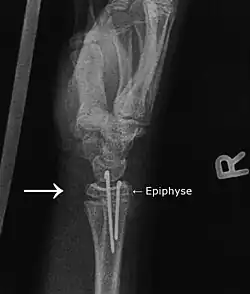

Der gleiche Patient wie oben nach Operation, Osteosynthese mittels Kirschnerdrähten.

Das rechte Bild zeigt die Situation nach der Operation. Hier wurden Drähte (sogenannte Kirschnerdrähte) von handseitig während der Reposition (Wieder-in-Position-Bringen) durch die Epiphyse in den Radiusschaft gebohrt. Der Radius steht jetzt nicht mehr nach palmar vor. Die Kirschnerdrähte verbleiben, bis die Epiphyse wieder festgewachsen ist (2–4 Wochen).